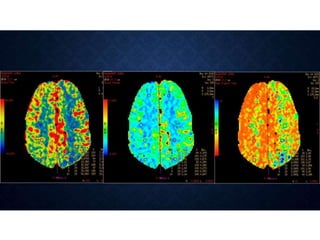

 Color-coded perfusion maps of cerebral blood volume,

cerebral blood flow, and mean transit time are then generated

at the workstation

 Both thearterial and the venous ROIs are chosen in large vessels that course in a direction nearly perpendicular to the plane of CT acquisition (the axial plane).  Color-coded perfusion maps of cerebral blood volume, cerebral blood flow, and mean transit time are then generated at the workstation